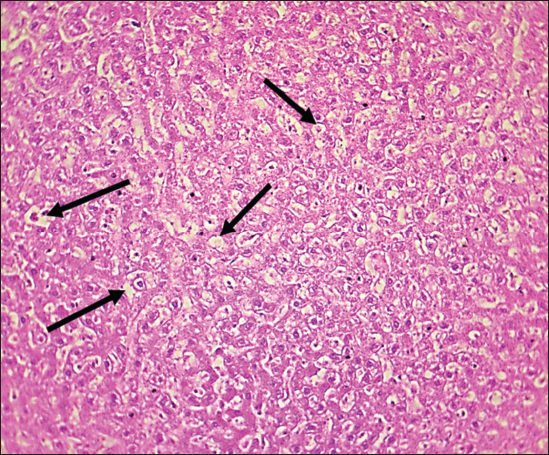

Fig. 1. Histological section of liver in rats of the control group. The section shows a normal histological structure for the hepatic sinusoid without any significant occupied lesion (H and E stain 100X).

Fig. 2. Histological section of liver in rats drenched with 0.6 mg/kg citalopram and treated with 10 mg/kg J. regia pulp extract. The section shows the normal histological structure of hepatic tissue without any significant occupied lesion (H and E stain 100X).

Fig. 3. Histological section of liver in rats drenched with 0.6 mg/kg citalopram and treated with 20 mg/ kg J. regia pulp extract. The section shows the normal histological structure of hepatic tissue without any significant occupied lesion (H and E stain 100X).